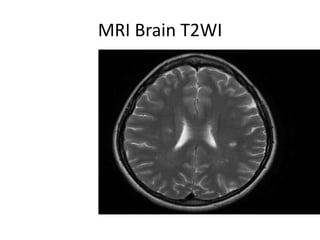

MRI Brain T2WI

• MRI: Periventricular, brainstem, juxtacortical

prominent T2, often Gad enhancing lesions, T1

hypointense (black holes)